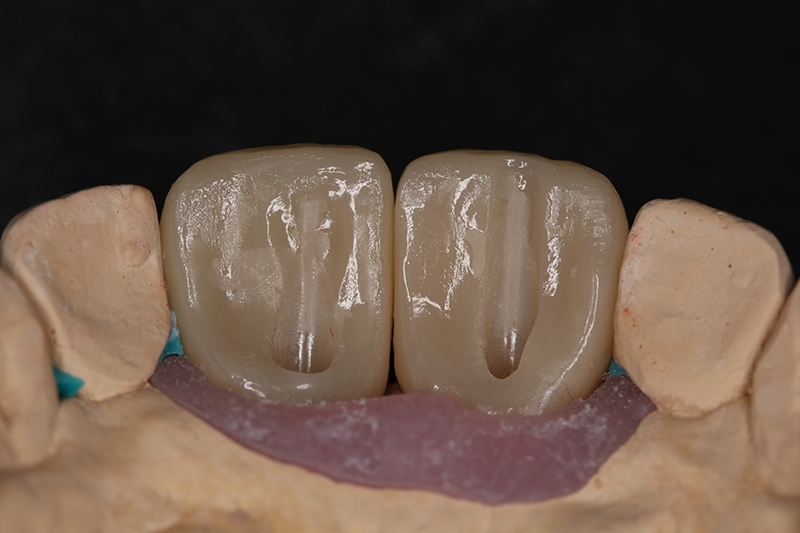

植牙全瓷冠假牙

假牙與顎側面維修開孔

3個月時間臨時假牙塑形牙齦

鎖入正式全瓷冠假牙

門牙植牙全瓷冠+側門牙全瓷冠完成照